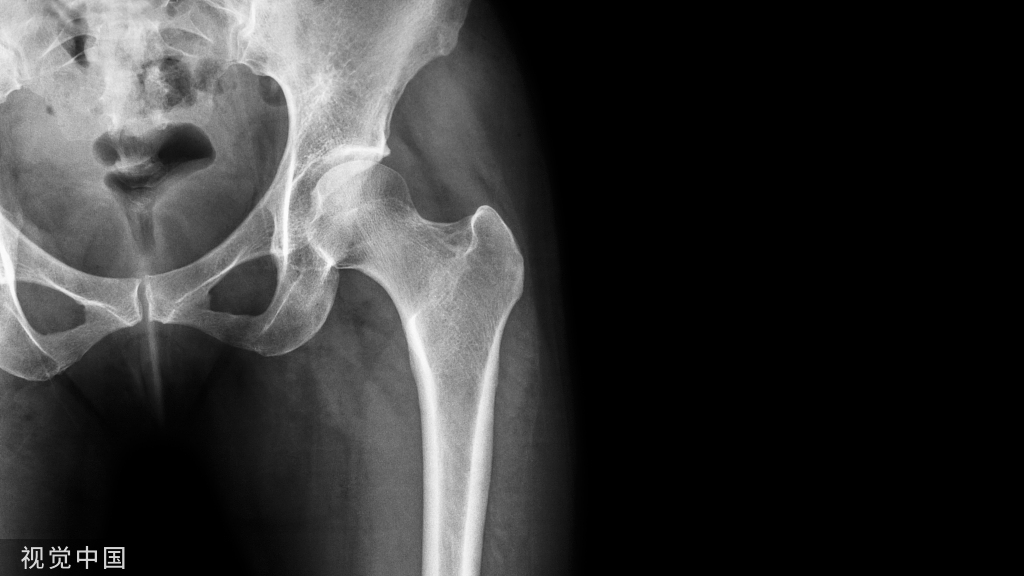

疾病症状

(1)骨折端有异常活动:骨折在6个月以上,作骨折端活动检查时,若有异常活动,即可诊断为骨不连。

(2)疼痛:骨端在移动时或试做负重时,产生疼痛。

(3)畸形与肌萎缩:未连接的骨折,可有成角、缩短与旋转畸形。由于长期不能使用肢体,关节挛缩畸形与肌萎缩都可出现。

(4)负重功能丧失:骨干骨折后的骨不连负重功能丧失,但某些股骨颈骨折有跛行。

(5)骨传导音降低:骨不连或延迟连接,骨传导音较健侧弱。